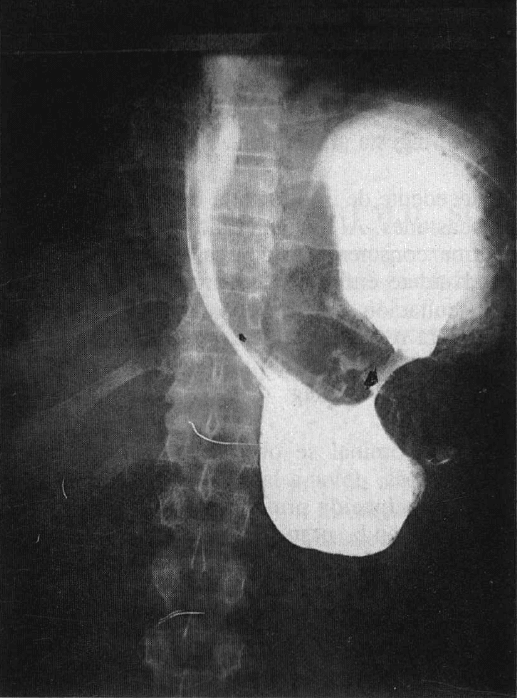

En la radiografía del tórax se encontró una imagen que sugirió una eventración o hernia diafragmática (Fig. 3). La endoscopia digestiva alta comprobó disminución de la luz al nivel del cuerpo gástrico, e imposibilidad de explorar la región antral; se pensó en un síndrome pilórico. En la serie gastroduodenal se visualizó una imagen compatible con vólvulo gástrico (Fig. 4). Con base en estos hallazgos y los antecedentes del paciente, se hace el diagnóstico de vólvulo

Fig. 3. Radiografía del tórax que muestra una imagen sugestiva de

alteración anatómica de tipo eventración o hernia diafragmática (flechas grandes).

Fig. 4. Serie gastroduodenal en donde se observa detención

del medio en la región inferior, y forma afilada del esófago (flecha pequeña)

con bloqueo en el sitio del vólvulo (flecha grande).